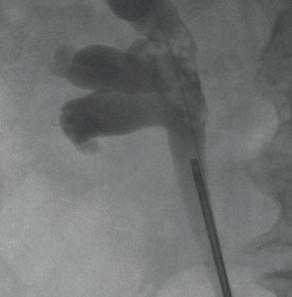

Die Photodynamische Diagnostik (PDD) verbessert die Darstellung des Tumorbereichs während der Blasenspiegelung. © Ordensklinikum Linz

Tumor im Nierenbecken als Kontrastaussparung sichtbar. Papillärer Tumor im Harnleiter (Führungsdraht ebenfalls auf dem Bild zu sehen). Papillärer, blutender Tumor im Nierenbecken (Führungsdraht auf den Bildern zu sehen).

Nierenbecken nach Tumorlaserung mit liegendem HL-Stent. © Ordensklinikum Linz

© Ordensklinikum Linz © Ordensklinikum Linz © Ordensklinikum Linz © Ordensklinikum Linz